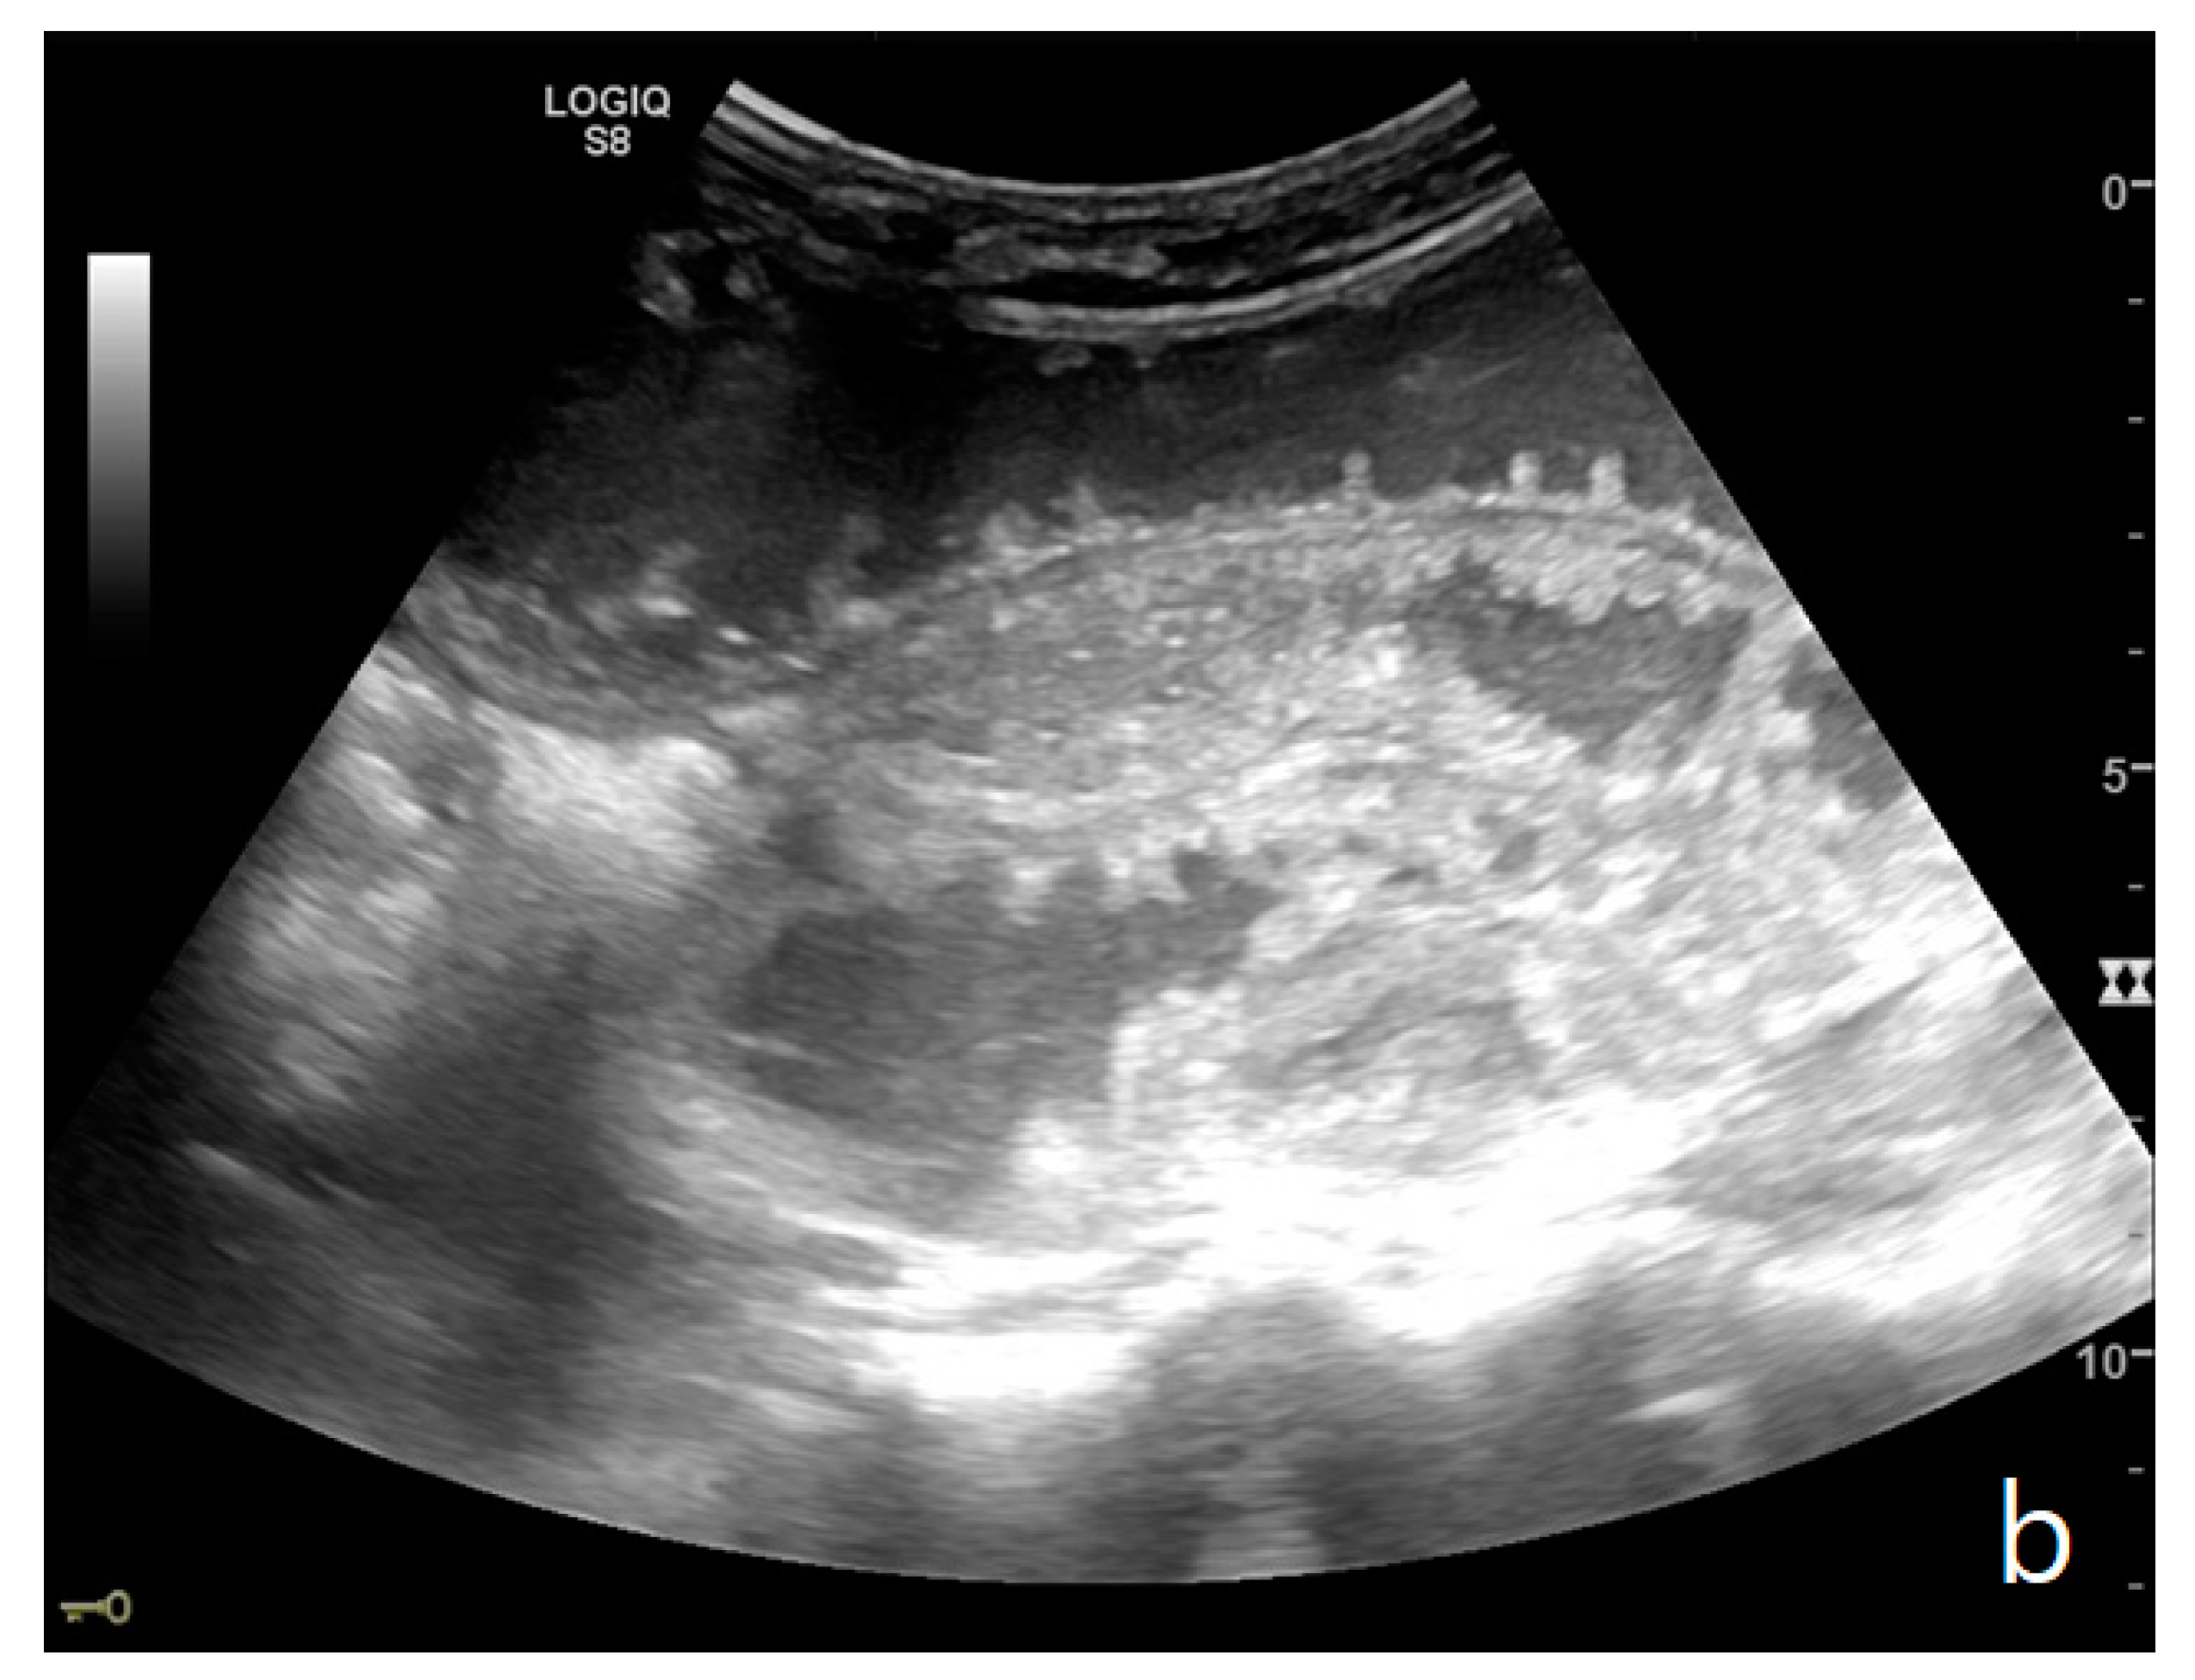

Figure 5.

A complicated SBO presenting fluid-filled bowel loops with thickened walls with a stratified echo pattern (a) and thickened valvulae conniventes (b). Free fluid in the abdominal cavity was detected (b). Tail comet artifacts for air-fluid levels are visible (a). At the time of surgery, the bowel loop was necrotic.